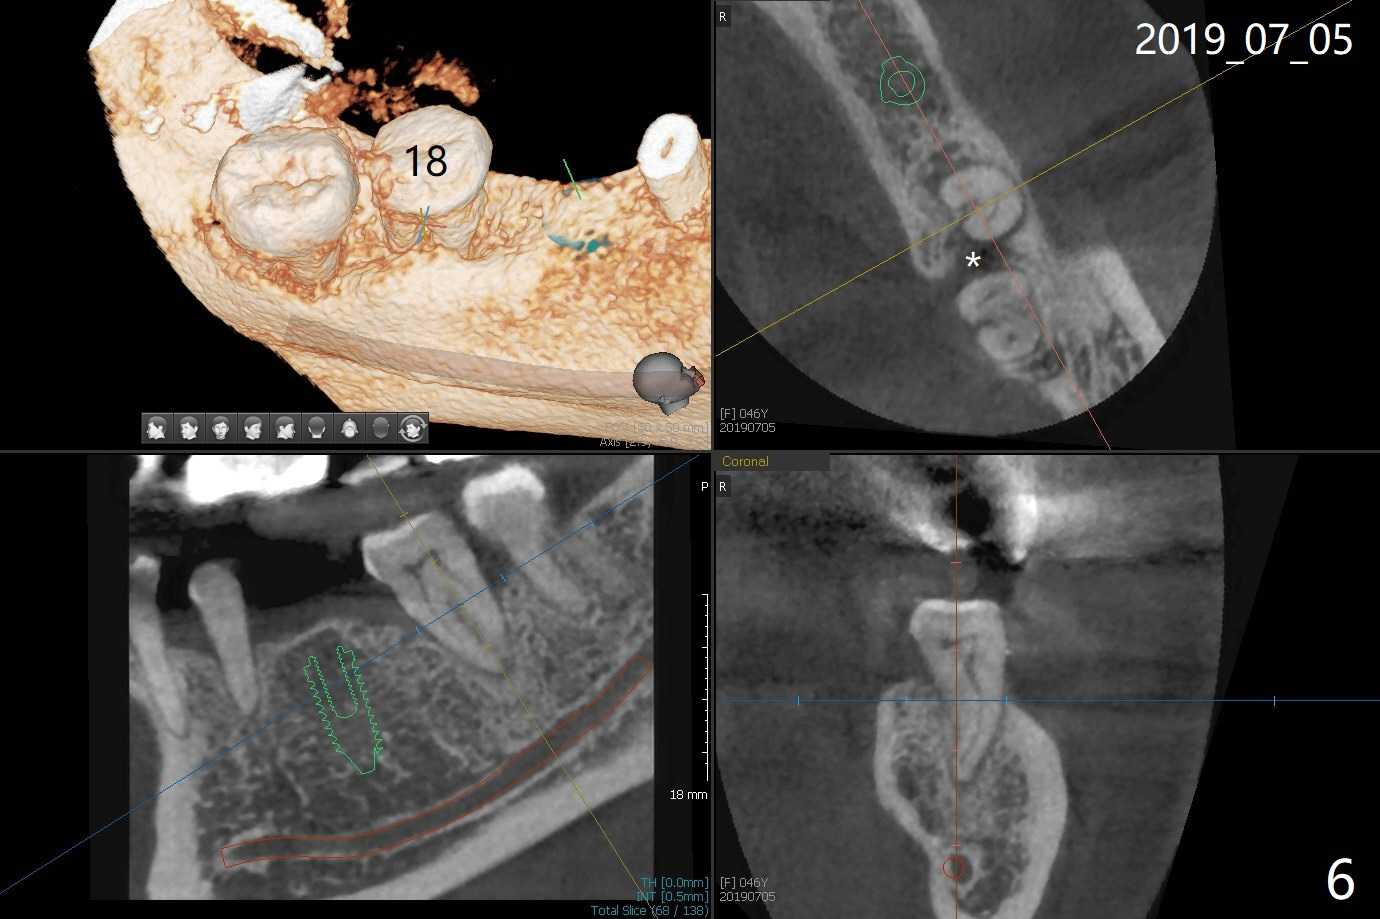

A 46-year-old woman had severe periodontal abscess lingual to #18-20 FPD a year ago (Fig.1,2 *). After SRP and Arestin placement #18 ML, the FPD was sectioned (Fig.2 >) to determine which abutment is to be extracted for implant. Since the sectioning, the patient has been unable to masticate on the left side (Fig.3). With removal of the FPD, CT is taken for surgical guide. Are the abutments salvageable (Fig.4,6)?